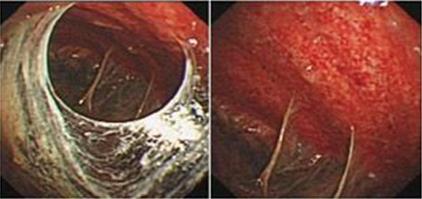

结核性胸膜炎的胸腔镜下表现